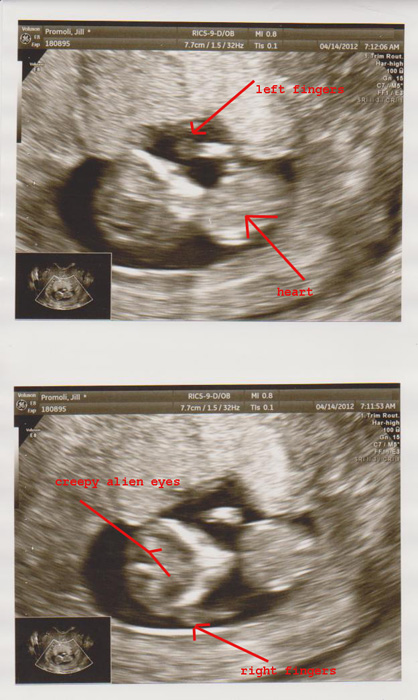

We got the best news of our lives again in February, and while we were cautious we couldn’t have been more excited. It was a terrifyingly complicated first trimester that had me back and forth to the hospital and doctor’s office, but despite all of the chaos Maude (a nickname with a long story that’s probably only funny to us) was doing amazing. A little behind on size, but with a glorious little heartbeat. We watched that little baby grow every week from fetal pole to gummi bear to baby. At eleven weeks he was perfect. We counted all of his little fingers (ten!) and watched him dance, and there was no reason to think that after our NT scan the next Friday that we wouldn’t be sharing the big news with all of our friends at a party the next day. Life was good. This was really happening. There was going to be another baby.

On April 20th the sky fell. We left Isla with her grandparents and happily set off for Toronto for our NT scan and a lunch date. We went in for the ultrasound and at first everything seemed perfect, but then something seemed off with the tech. I know her well and she’s given me plenty of good and bad news over the years, and that day her face told me it was a bad news day. She brought in two more techs to discuss what they were seeing while Craig and I waited in terror trying to understand what was happening. We caught snippets of discussion. “No fingers,” (but there were fingers last week?). “Face looks wrong,” (what does ‘wrong’ mean?). “Problem with the legs,” (those legs that have danced and kicked for all this time?). “The good news is that the nuchal fold looks good, so Down Syndrome probably isn’t an issue,” (but… what the hell is happening in there?).